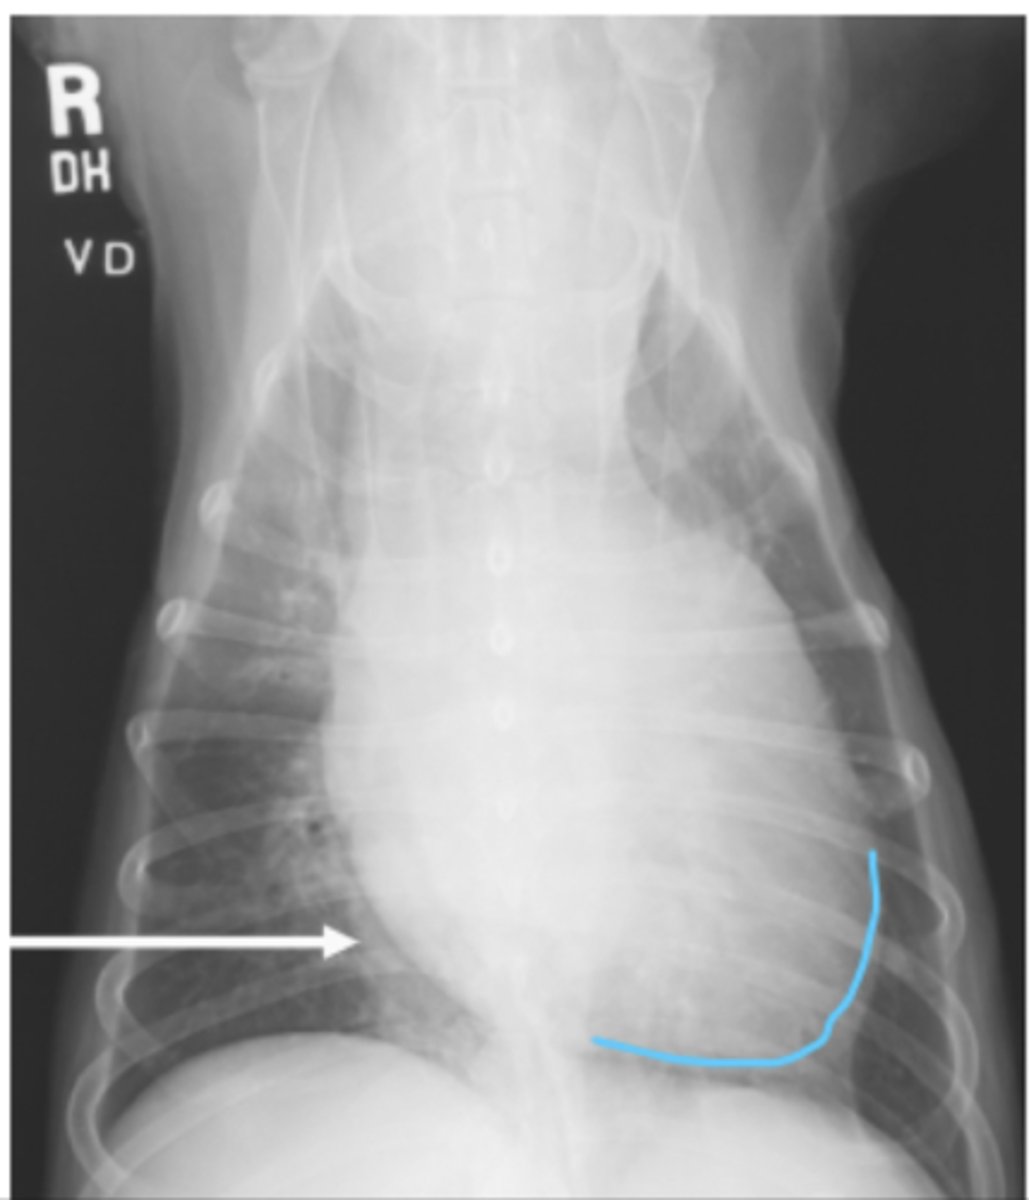

efusión pleural

patología: